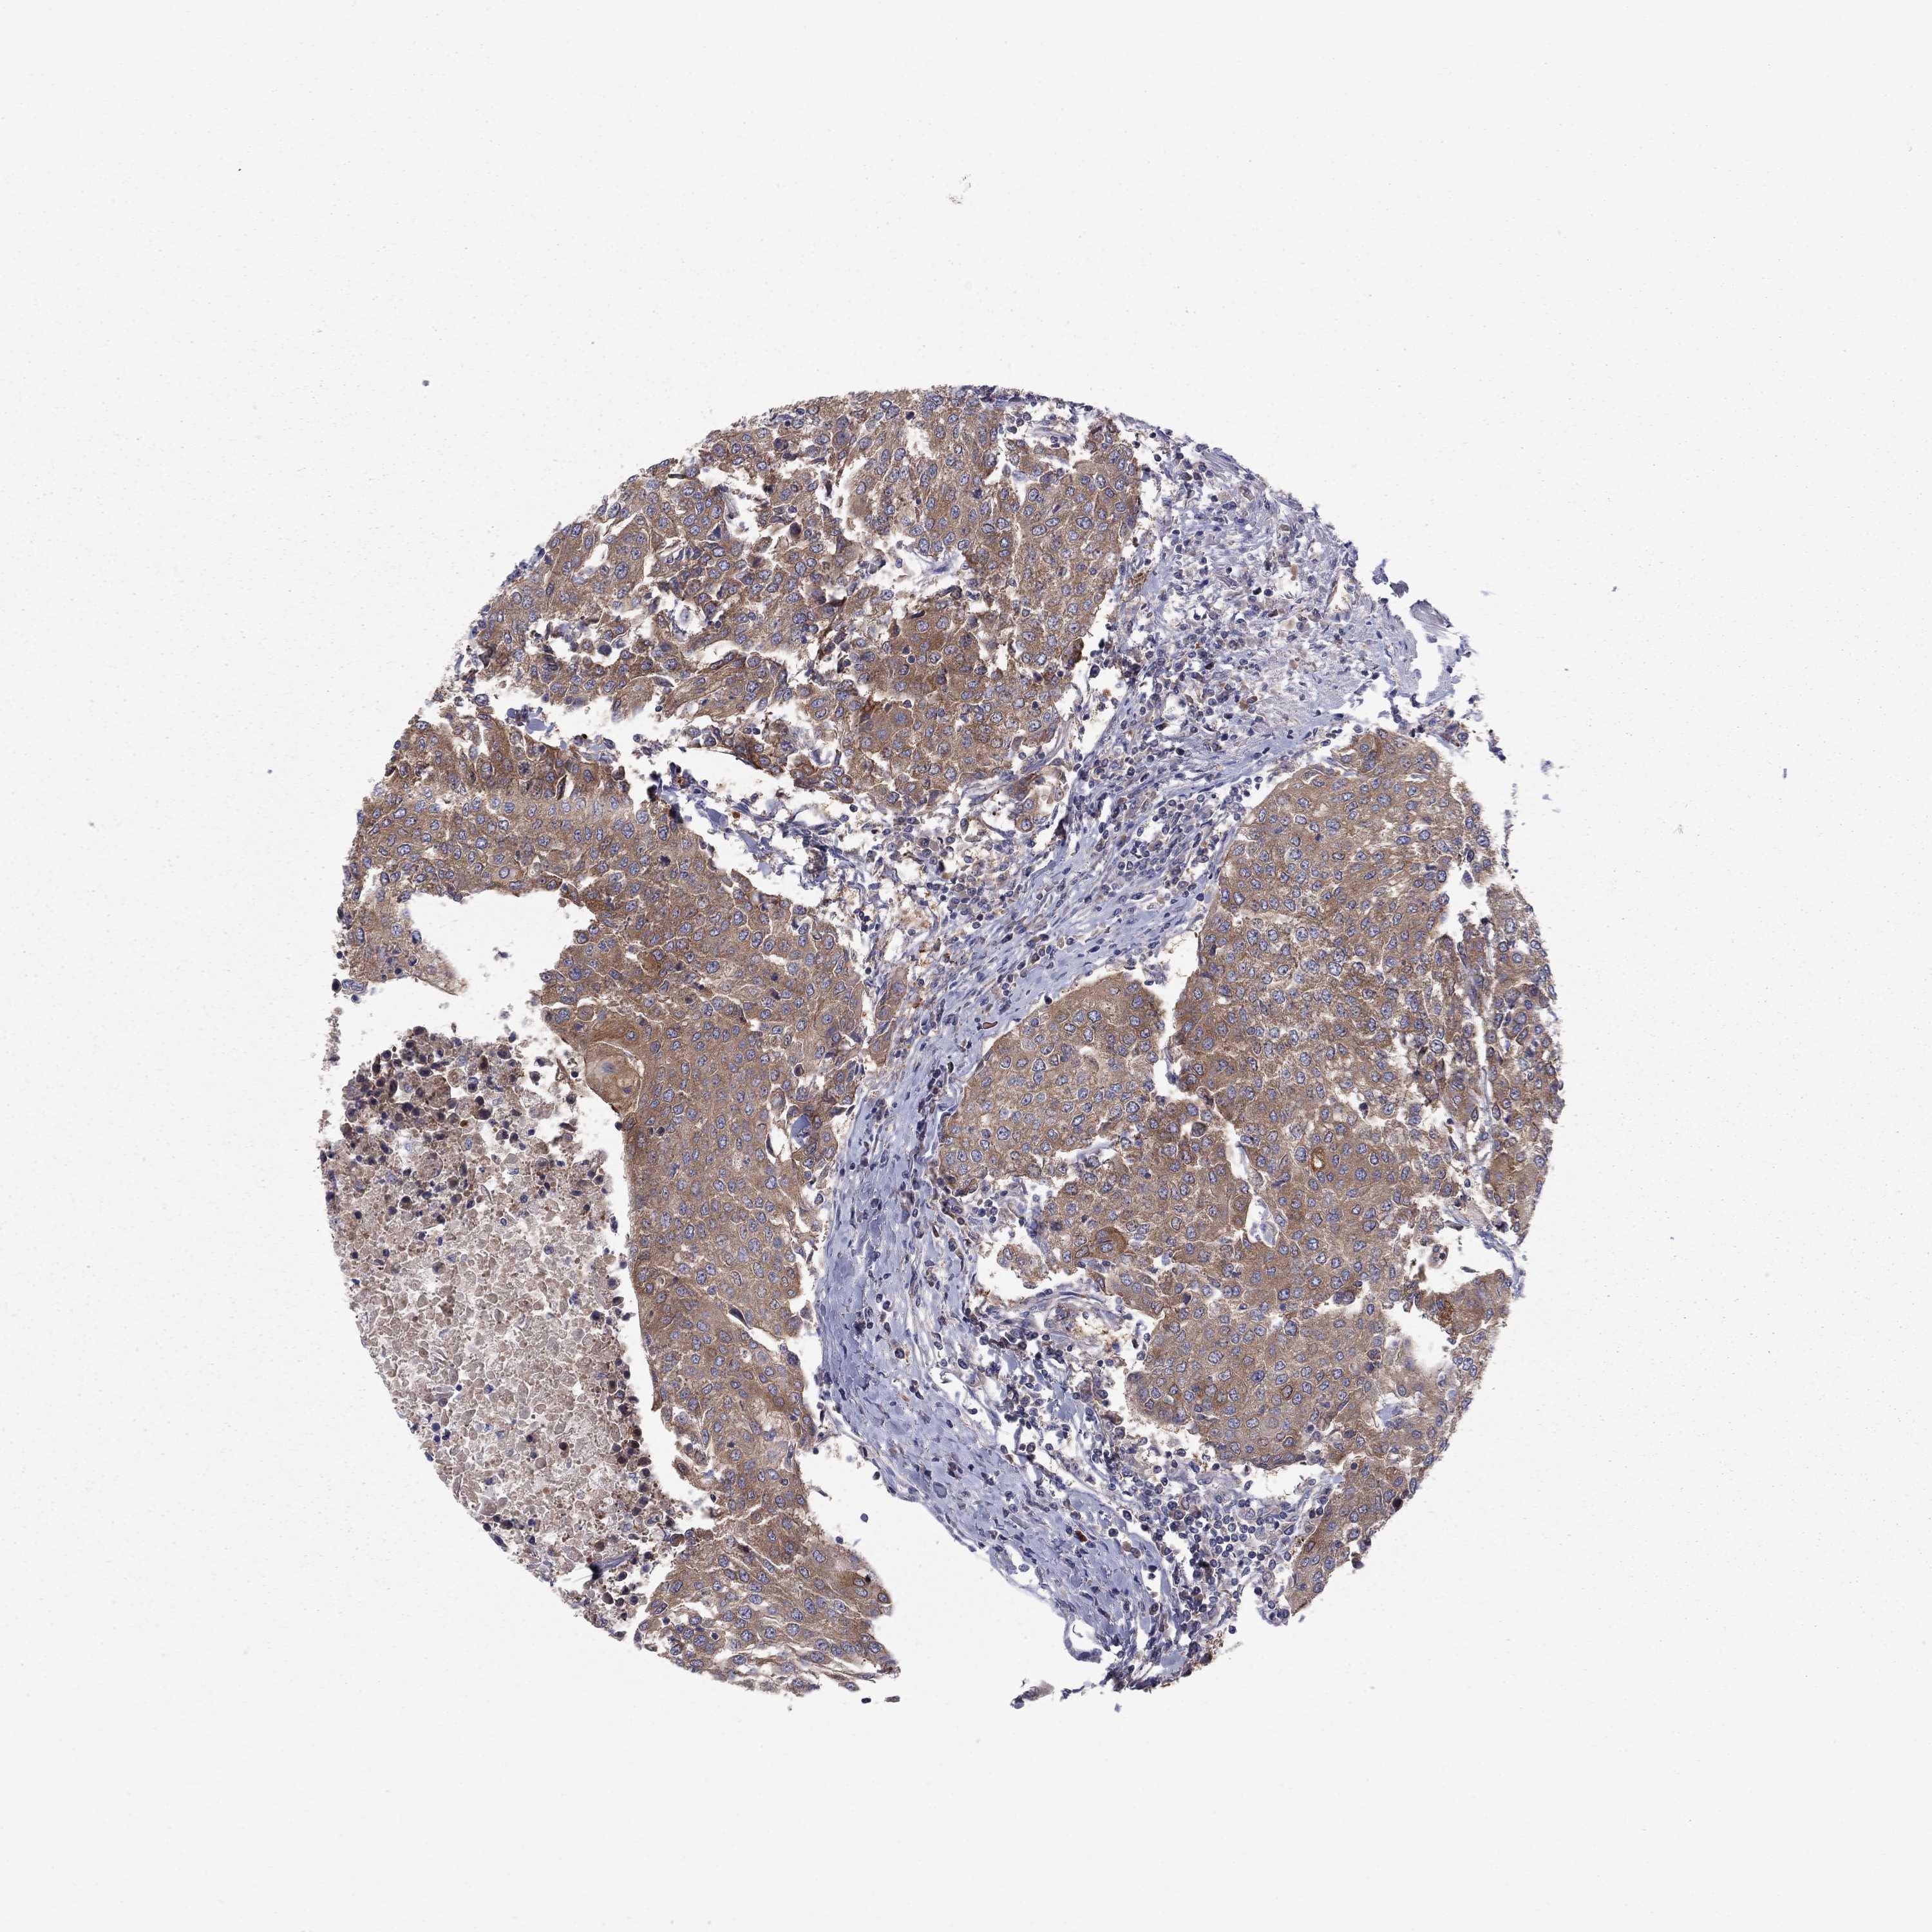

UROTHELIAL CANCER - Protein expressioni

A mouse-over function shows sample information and annotation data. Click on an image to view it in a full screen mode. Samples can be filtered based on level of antibody staining by selecting one or several of the following categories: high, medium, low and not detected. The assay and annotation is described here.

Note that samples used for immunohistochemistry by the Human Protein Atlas do not correspond to samples in the TCGA dataset.

Antibody stainingi

Antibody staining in the annotated cell types in the current human tissue is reported as not detected, low, medium, or high, based on conventional immunohistochemistry profiling in selected tissues. This score is based on the combination of the staining intensity and fraction of stained cells.

Each image is clickable and will lead to virtual microscopy that enables deeper exploration of all samples and also displays staining intensity scores, fraction scores and subcellular localization as well as patient and tissue information for each sample.

Antibody HPA065983

Antibody HPA071879

Staining

High

Medium

Low

Not detected

Intensity

Strong

Moderate

Weak

Negative

Quantity

>75%

75%-25%

<25%

None

Location

Nuclear

Cytoplasmic/membranous

Cytoplasmic/membranous,nuclear

Urothelial carcinoma, High grade

Urothelial carcinoma, Low grade